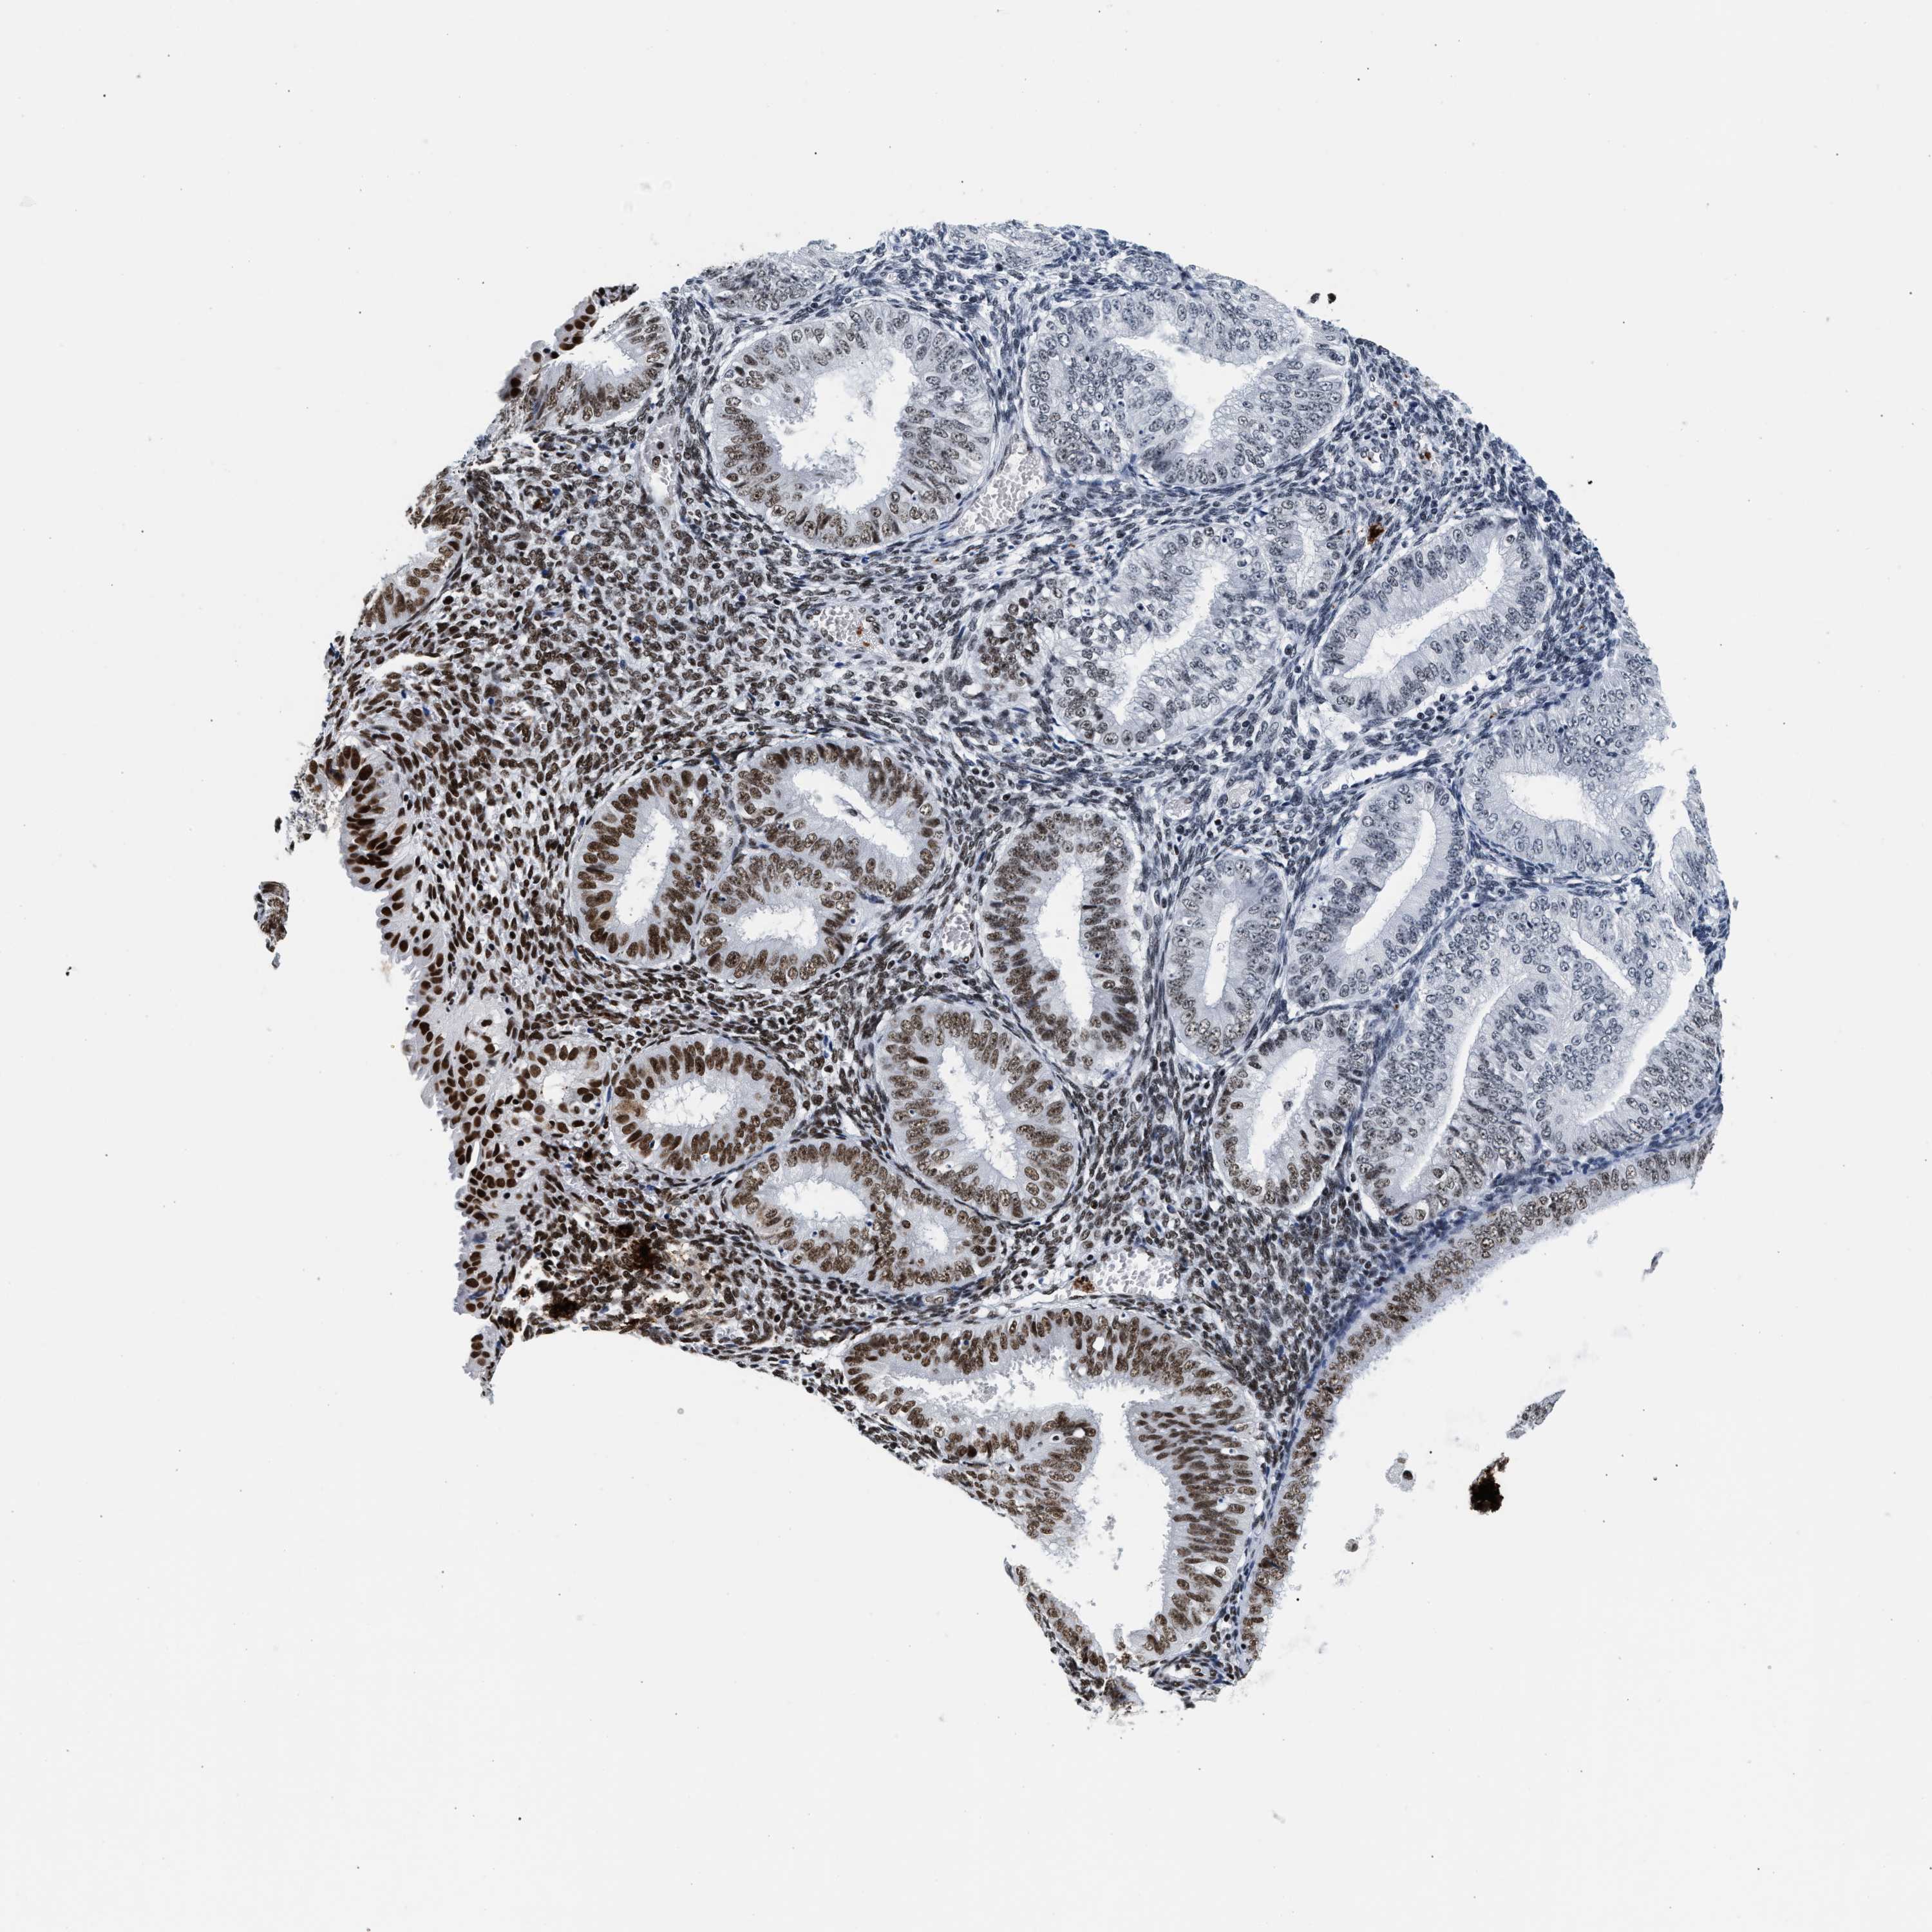

ENDOMETRIAL CANCER - Protein expressioni

A mouse-over function shows sample information and annotation data. Click on an image to view it in a full screen mode. Samples can be filtered based on level of antibody staining by selecting one or several of the following categories: high, medium, low and not detected. The assay and annotation is described here.

Note that samples used for immunohistochemistry by the Human Protein Atlas do not correspond to samples in the TCGA dataset.

Antibody stainingi

Antibody staining in the annotated cell types in the current human tissue is reported as not detected, low, medium, or high, based on conventional immunohistochemistry profiling in selected tissues. This score is based on the combination of the staining intensity and fraction of stained cells.

Each image is clickable and will lead to virtual microscopy that enables deeper exploration of all samples and also displays staining intensity scores, fraction scores and subcellular localization as well as patient and tissue information for each sample.

Antibody HPA020044

Antibody CAB022065

Staining

High

Medium

Low

Not detected

Intensity

Strong

Moderate

Weak

Negative

Quantity

>75%

75%-25%

<25%

None

Location

Nuclear

Cytoplasmic/membranous

Cytoplasmic/membranous,nuclear

Adenocarcinoma, NOS

Adenoma, NOS